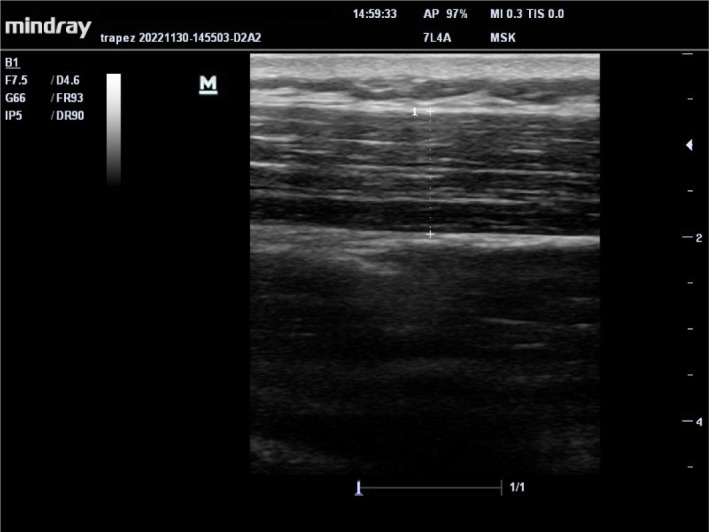

Methods: Twenty-two FMS patients and 18 asymptomatic control cases who applied to the physical medicine and rehabilitation outpatient clinic were included. The thickness of the gastrocnemius medialis/lateralis, trapezius, and upper arm muscle was evaluated with ultrasonography. Muscle strength was evaluated with hand grip strength, muscle performance with chair stand test (CST), walking performance with 10 m walking test, disease severity with Fibromyalgia Impact Questionnaire-Revised, pain severity with VAS, and kinesiophobia with TAMPA kinesiophobia scale.

Abstract Image